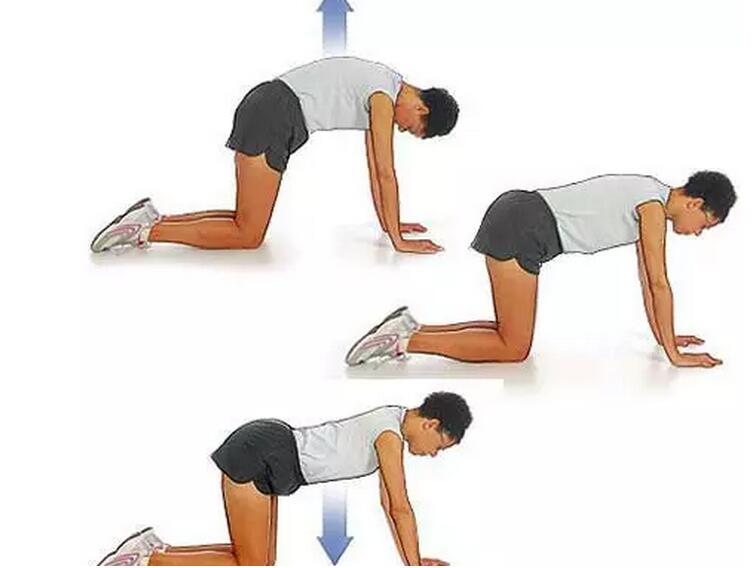

强直患者坚持运动中有哪些要注意

成都强直医院来解释那么强直性脊柱炎患者生活中应该注意哪些呢? ...